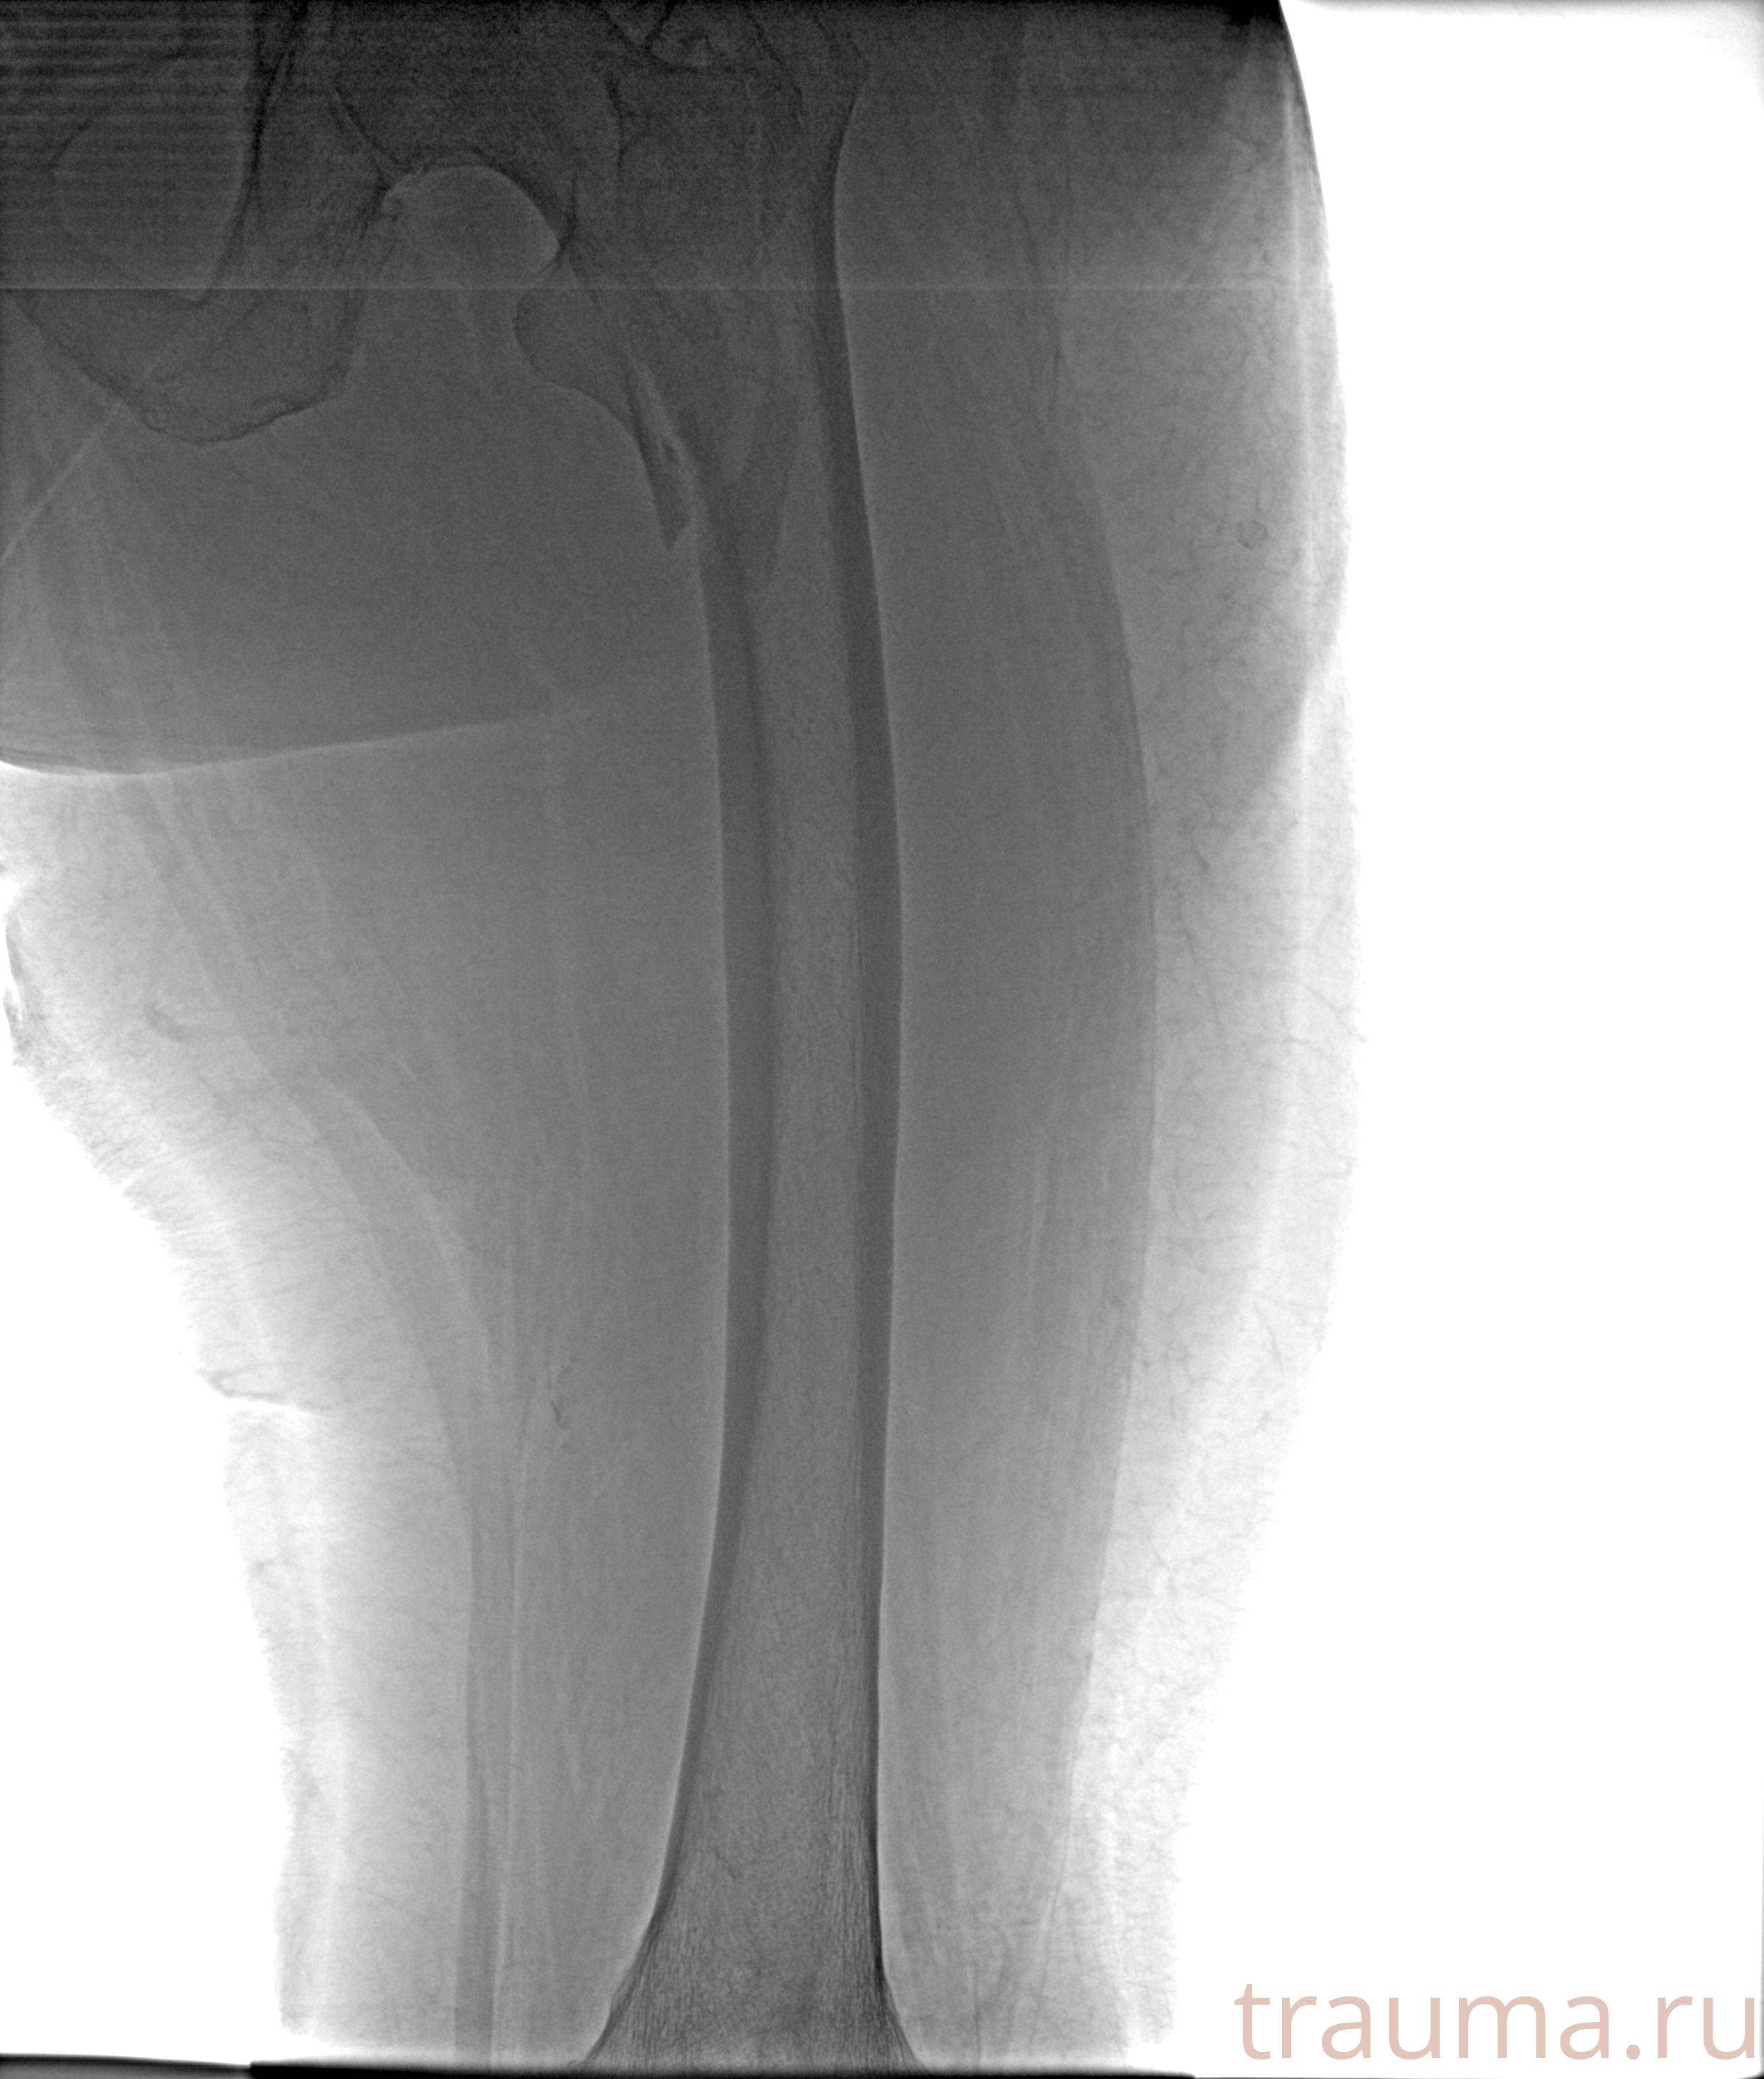

Рентгенограммы

Рентген на дому: по вашему адресу приезжает врач-рентгенолог, травматолог-ортопед с мобильным рентгеновским аппаратом, проводит диагностику травмы или заболевания, делает необходимые рентгенограммы, дает рекомендации по дальнейшему лечению. Получить качественные снимки в домашних условиях возможно благодаря уникальной методике, разработанной МосРентген Центром для института  Склифосовского